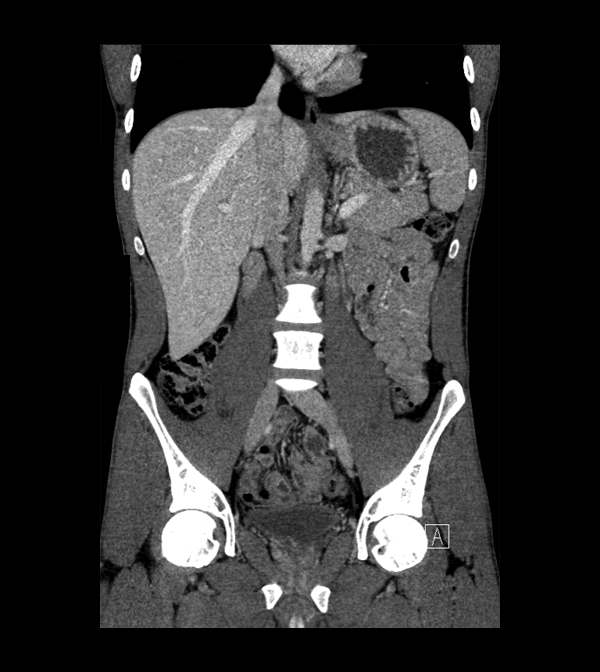

Body

Covers abdominal CT anatomy.